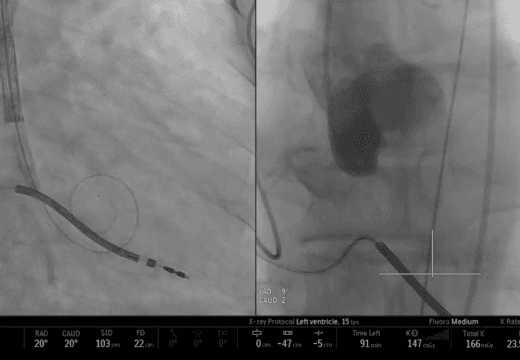

COMPLEX STRUCTURAL HEART

Multimodal display of devices gives proceduralists and teams a complete view of the entire case to refine processes, decision-making and future analysis.